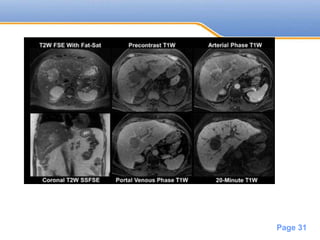

MRI

T1(variable)

T1 C+ (Gd)

Enhancement similar to CT

Rim enhancement may persist

T2 –Hyperintense

Post SPIO (Iron oxide) - increases sensitivity

in diagnosing small HCC’s

Powerpoint Templates

Page 31

• #32 A 3-cm lesion is seen near the porta hepatis within the right lobe of the liver. It is mildly hyperintense on T2-weighted imaging with fat suppression and is hypointense on precontrast T1-weighted imaging. The lesion demonstrates heterogeneous arterial-phase enhancement and subsequent washout on the portal venous phase. Delayed 20-minute hepatobiliary-phase imaging shows marked hypointensity of this lesion relative to the adjacent liver. HCC can have multiple and varied appearances. Typically, a focal HCC shows arterial-phase enhancement with subsequent washout on portal-venous-phase imaging, which is highly specific for HCC in the correct clinical setting. Dynamic enhanced imaging of HCC is extremely important for both detection and characterization of these lesions. Other useful imaging features to help characterize HCC include rim enhancement on portal-venous-phase imaging (and 5- to 10-minute delayed imaging using a conventional extracellular gadolinium-based contrast agent); hypointensity on precontrast T1 imaging; and isointensity or mild hyperintensity on T2 imaging. Moderate and poorly differentiated HCCs do not contain normal functioning hepatocytes and typically appear hypointense on delayed hepatobiliary-phase imaging, as in this case. There are reports of hepatobiliary gadolinium-based contrast uptake in well-differentiated hepatocellular carcinoma; however, this effect is uncommon and not entirely understood. As in this example, the best contrast between lesion and the adjacent liver is achieved on the delayed hepatobiliary phase. However, delayed hepatobiliary-phase imaging is inadequate for characterization of HCC, which requires the constellation of imaging findings from all sequences for diagnosis. Thus, the utility of delayed hepatobiliary phase is to provide additional characterization as well as detection of these lesions, particularly smaller lesions. In general, the diagnosis of HCC should be made in the appropriate clinical setting, such as a high-risk patient with viral hepatitis or other risk factors for HCC. single-shot fast spin-echo MRI